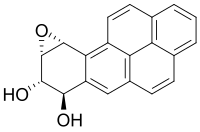

Smoke contains several carcinogenic pyrolytic products that bind to DNA and cause genetic mutations. Particularly potent carcinogens are polycyclic aromatic hydrocarbons (PAH), which are toxicated to mutagenic epoxides. The first PAH to be identified as a carcinogen in tobacco smoke was benzopyrene, which has been shown to toxicate into an epoxide that irreversibly attaches to a cell's nuclear DNA, which may either kill the cell or cause a genetic mutation. If the mutation inhibits programmed cell death, the cell can survive to become a cancer cell. Similarly, acrolein, which is abundant in tobacco smoke, also irreversibly binds to DNA, causes mutations and thus also cancer. However, it needs no activation to become carcinogenic.[220]

- Polycyclic aromatic hydrocarbons are tar components produced by pyrolysis in smoldering organic matter and emitted into smoke. Several of these PAH's are already toxic in their normal form, however, many of then can become more toxic to the liver. Due to the hydrophobic nature of PAH's they do not dissolve in water and are hard to expel from the body. In order to make the PAH more soluble in water, the liver creates an enzyme called Cytochrome P450 which adds an additional oxygen to the PAH, turning it into a mutagenic epoxides, which is more soluble, but also more reactive.[222] The first PAH to be identified as a carcinogen in tobacco smoke was benzopyrene, which been shown to toxicate into a diol epoxide and then permanently attach to nuclear DNA, which may either kill the cell or cause a genetic mutation. The DNA contains the information on how the cell function; in practice, it contains the recipes for protein synthesis. If the mutation inhibits programmed cell death, the cell can survive to become a cancer, a cell that does not function like a normal cell. The carcinogenicity is radiomimetic, i.e. similar to that produced by ionizing nuclear radiation. Tobacco manufacturers have experimented with combustion less vaporizer technology to allow cigarettes to be consumed without the formation of carcinogenic benzopyrenes.[223] Although such products have become increasingly popular, they still represent a very small fraction of the market, and no conclusive evidence has shown to prove or disprove the positive health claims.